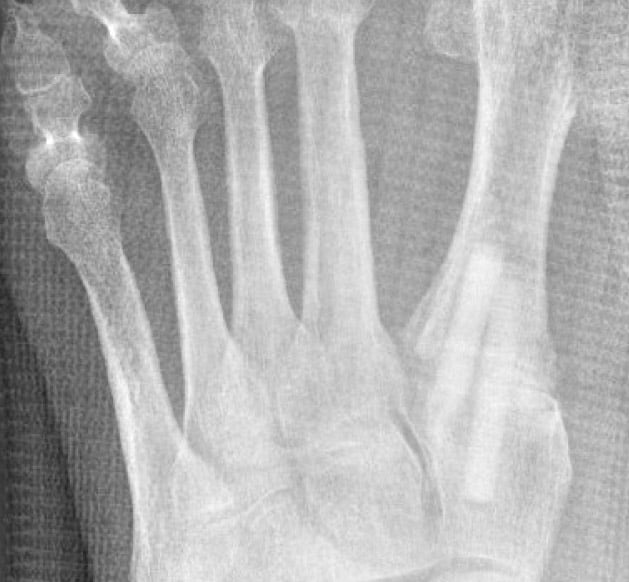

X-ray postoperatively ap

Correction by TMT I osteotomy and lapidus arthrodesis with 2 Shark Screw® grafts